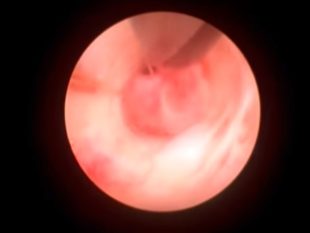

This video features a 3cm polypectomy resection with the MyoSure device.

In this video, a 2cm myoma is removed from a 40-year-old patient with the MyoSure device.

In this video, a 1.5cm myoma is removed from a 41-year-old patient with the MyoSure device.

In this training video, Dr. Robert K. Zurawin performs hysteroscopy with removal of retained products of conception using the MyoSure XL Tissue Removal System.

In this training video, Dr. Samantha Houser demonstrates window placement technique during a polypectomy and underneath polypectomy with the MyoSure device.

In this training video, Dr. Burt Geer demonstrates polypectomy and endometrial sampling with the MyoSure device.